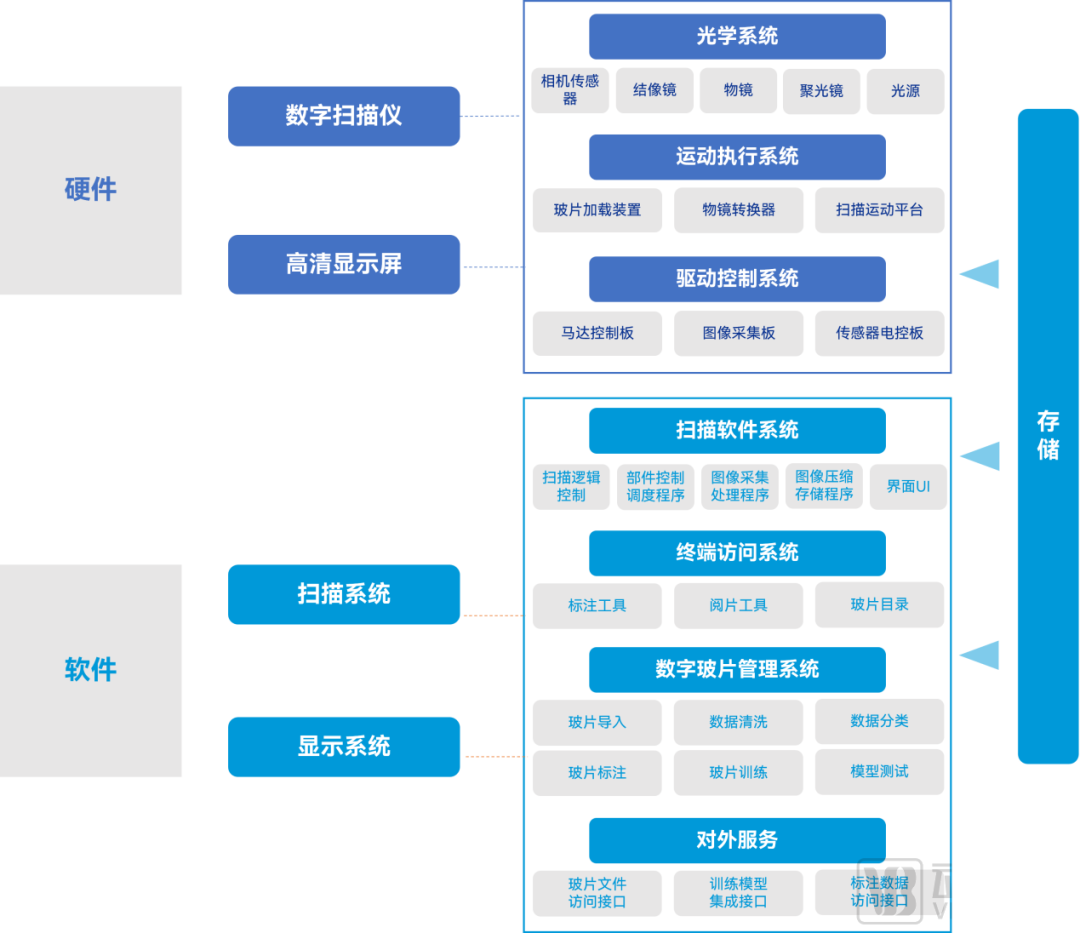

数字化病理科建设模块介绍

数字化建设模块图

来源:蛋壳研究院